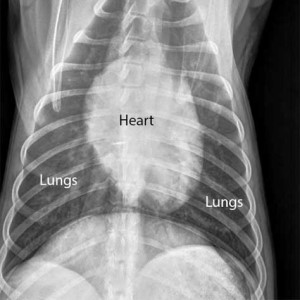

Radiology